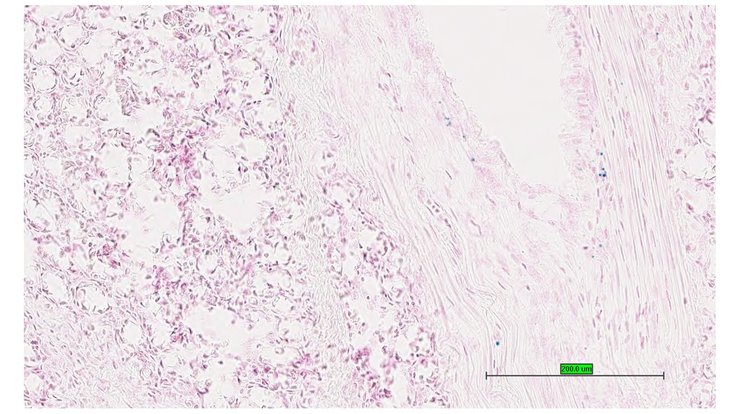

TS28: jejunum Present UC Davis_1879390

Specimen UC Davis_1879391: postnatal adult; Cnga3tm1.1(KOMP)Vlcg/Cnga3+ (more )

Structure Level Pattern Image Note

TS28: ileum Present UC Davis_1879391